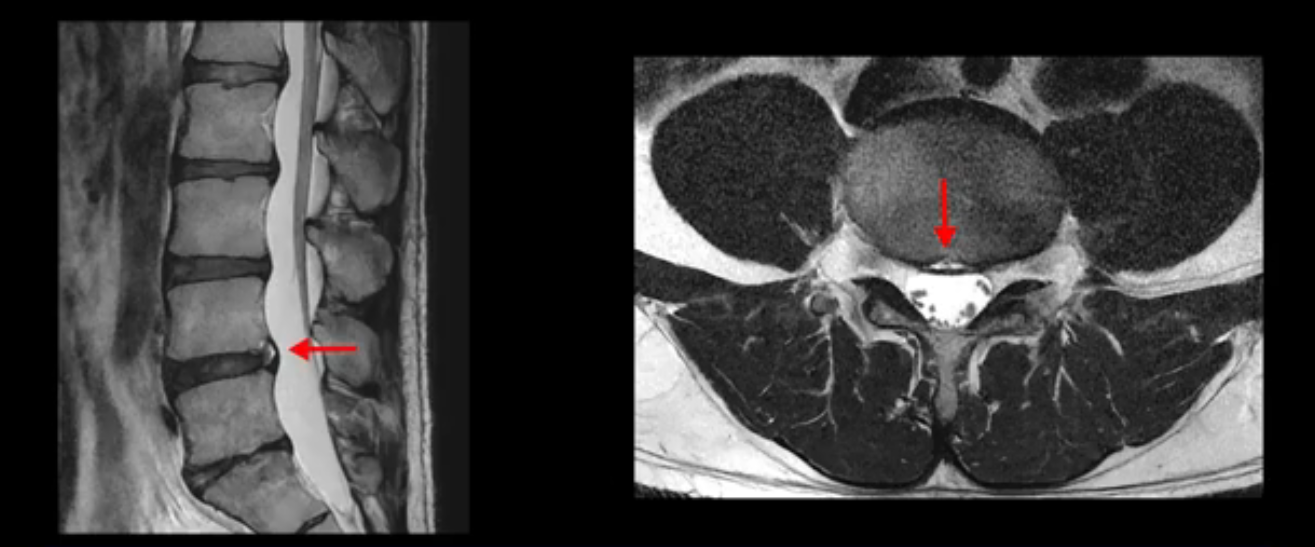

이분은 어떤 한 병원에서 디스크 내장증 얘기를 들으셨는데요. 여기 보시는 것처럼 4번 5번의 하얀 HIZ(High Intensity Zone)을 보고 디스크 내장증의 근거로 얘기하는 병원들이 있는데,

이 HIZ는 섬유륜이 찢어졌다가 이미 아문 뒤에도 얼마든지 보일 수 있는 흔적일 가능성이 있어서 재채기를 하면 아픈지, 허리를 구부릴 때 날카로운 통증이 생기는가 등의 증상으로 구별해야 하는데 MRI만 보고 HIZ가 보이면 그게 마치 통증의 원인인 것처럼 얘기하는 의사들이 있습니다. 이분 MRI를 자세히 보고 증상을 정말 자세히 들어본 의사가 있었더라면 다른 환자분들처럼 증상과 MRI가 일치하지 않는다는 얘기를 들을 수 있었을 텐데 이분은 그런 얘기는 듣지 못했습니다.